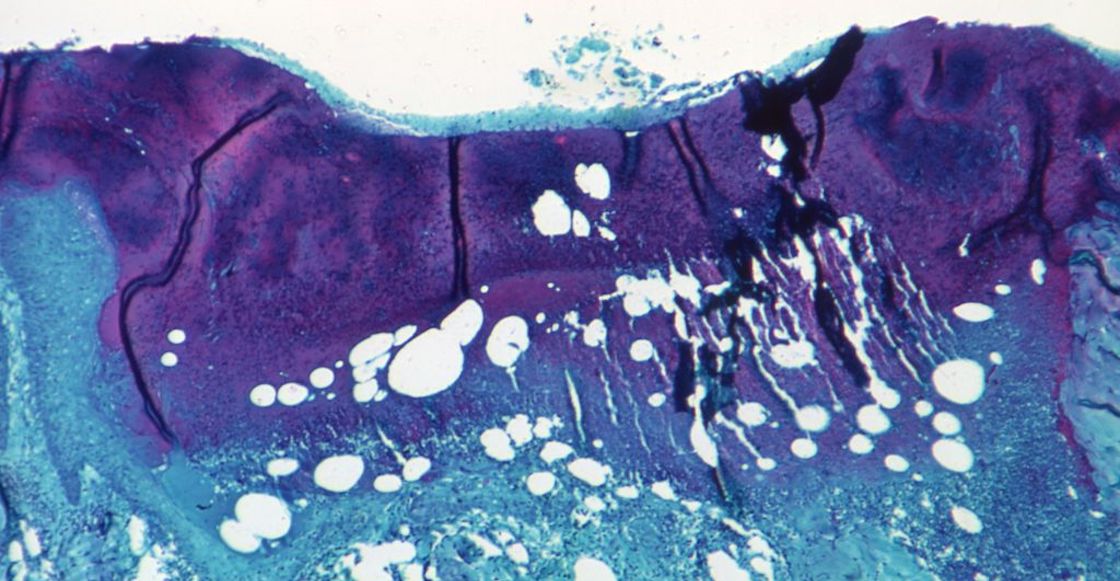

“Un técnico de laboratorio médico muestra una muestra sospechosa de viruela símica en el laboratorio de microbiología del Hospital La Paz el 6 de junio de 2022 en Madrid”. Foto: Pablo Blazquez Dominguez-Getty Images.